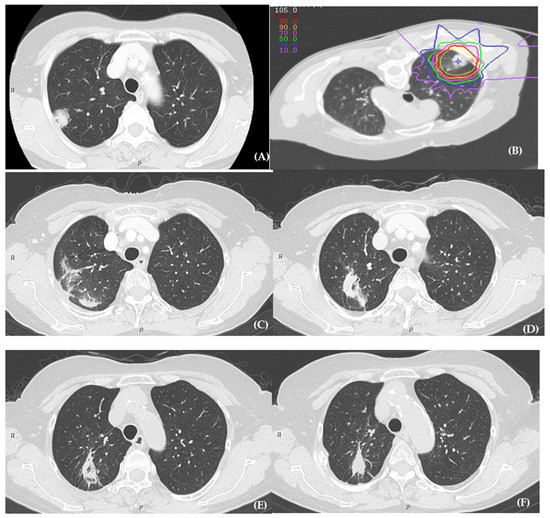

Cancers Free FullText The Risk Factors for Radiation Pneumonitis Can Pneumonia Cause Lung Cancer It’s caused by harmful cells in your lungs growing. With adenocarcinomas — the most common type of lung cancer —. Web patients with lung cancer are at an increased risk of developing some type of lung infection, including pneumonia. Web it’s estimated that over half of people with lung cancer develop lung infections, including pneumonia. Lung cancer is the third. Can Pneumonia Cause Lung Cancer.